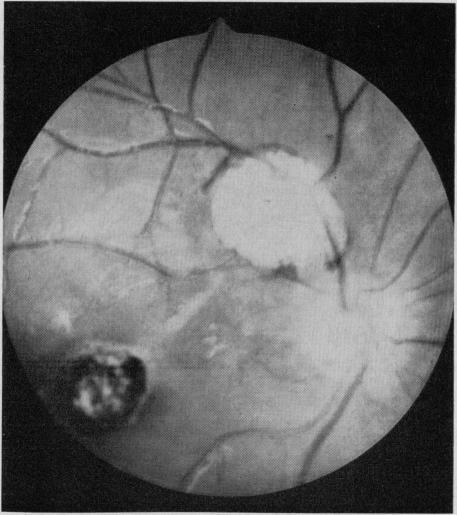

Endogenous uveitis in 117 children aged 15 years or under was investigated at The Hospital for Sick Children, Toronto, in a 12-year period from 1953 to 1964. This group included 55 children with anterior uveitis, 59 with posterior uveitis, and three with diffuse uveitis. An etiologic diagnosis could be made or the uveitis recognized as part of a definite clinical syndrome in approximately 47% of the 117 children. The commonest cause of posterior uveitis was toxoplasmosis and the commonest associated finding in anterior uveitis was juvenile rheumatoid arthritis. Chronic cyclitis of unknown etiology was a relatively common disease.

1953年至1964年的12年间,多伦多病童医院对117名15岁及以下儿童的内源性葡萄膜炎进行了调查。该组包括55名前葡萄膜炎患儿、59名后葡萄膜炎患儿和3名弥漫性葡萄膜炎患儿。在这117名儿童中,约47%的患儿可做出病因诊断或葡萄膜炎被认定为明确临床综合征的一部分。后葡萄膜炎最常见的病因是弓形虫病,前葡萄膜炎最常见的相关表现是青少年类风湿关节炎。病因不明的慢性睫状体炎是一种相对常见的疾病。